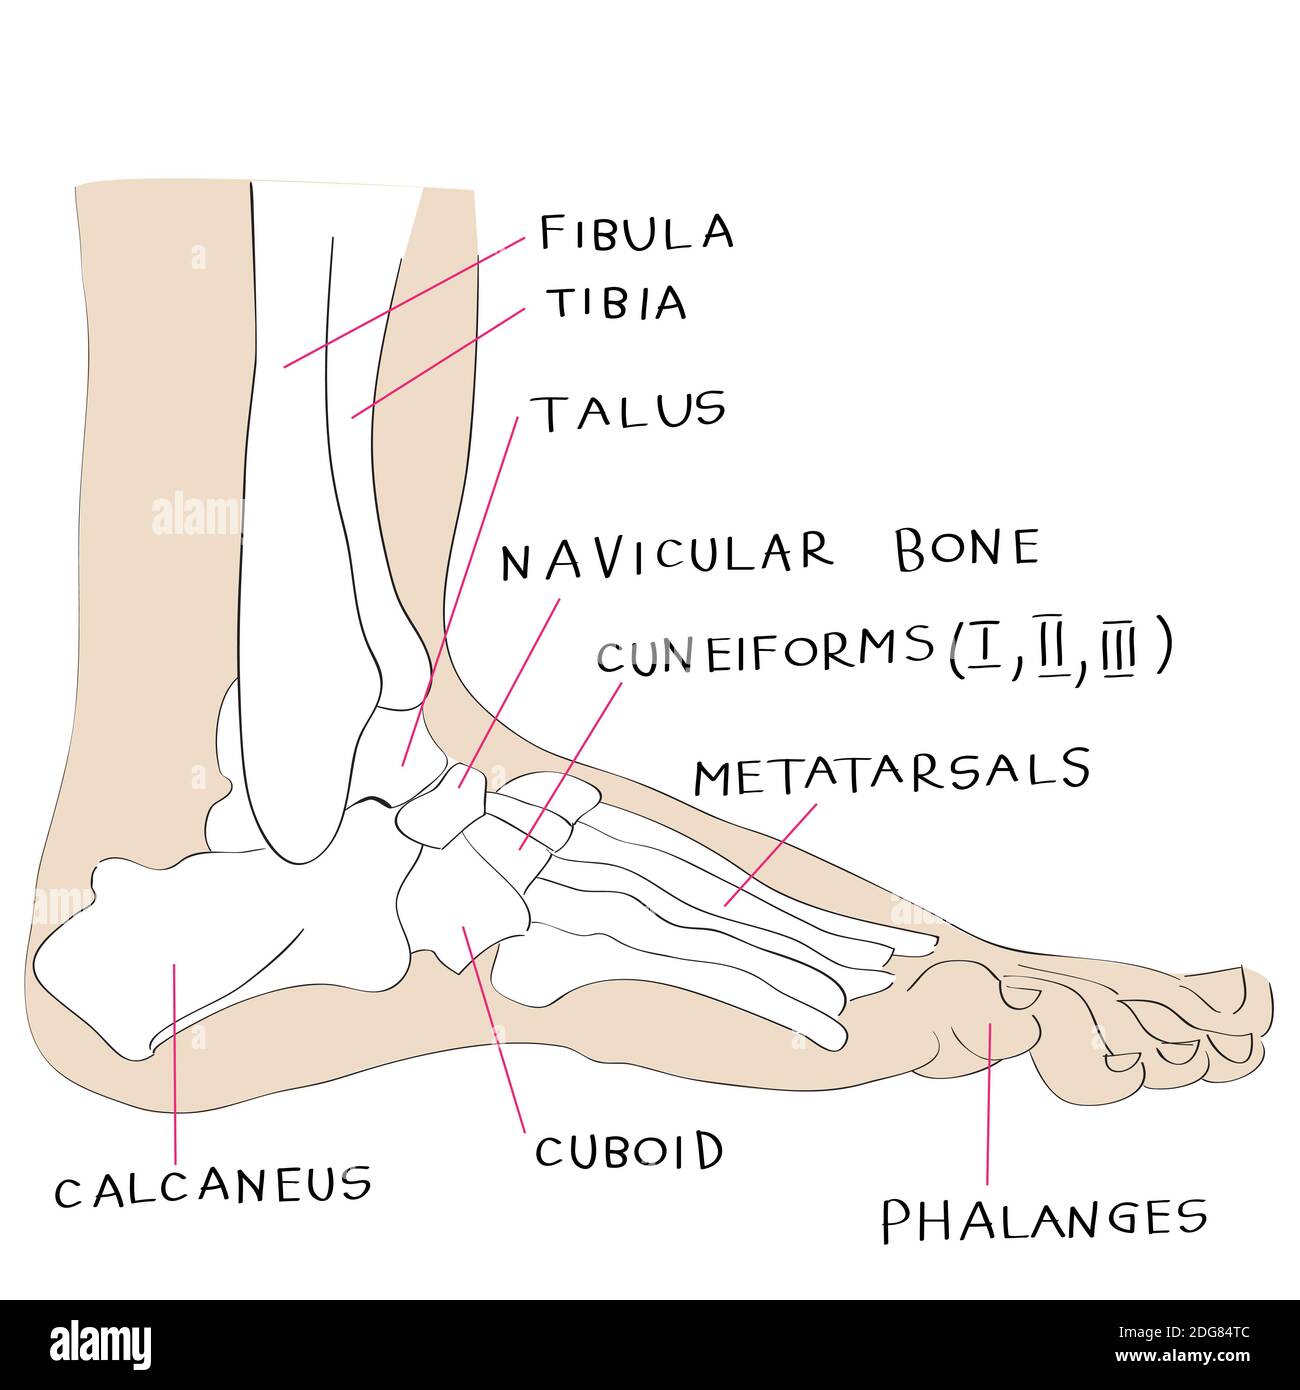

Il Piede - FISIOEDA

fisioeda.itpiede

fisioeda.itpiede

Vista Laterale Dell’anatomia Del Piede Immagini E Fotografie Stock Ad

www.alamy.itThe Anatomy Of The Foot Stock Illustration. Illustration Of Foot

www.alamy.itThe Anatomy Of The Foot Stock Illustration. Illustration Of Foot

Piede E Avampiede: Anatomia, Funzioni E Patologie In Sintesi | MEDICINA

medicinaonline.copiede osso scafoide anatomia cuboide ossa metatarso tarsale patologie funzioni avampiede tarso mediale caviglia netter articolazione processo accessorie prossimale falangi

medicinaonline.copiede osso scafoide anatomia cuboide ossa metatarso tarsale patologie funzioni avampiede tarso mediale caviglia netter articolazione processo accessorie prossimale falangi

Anatomia Del Piede: Studiamola Insieme | Sanitaria Bresciana